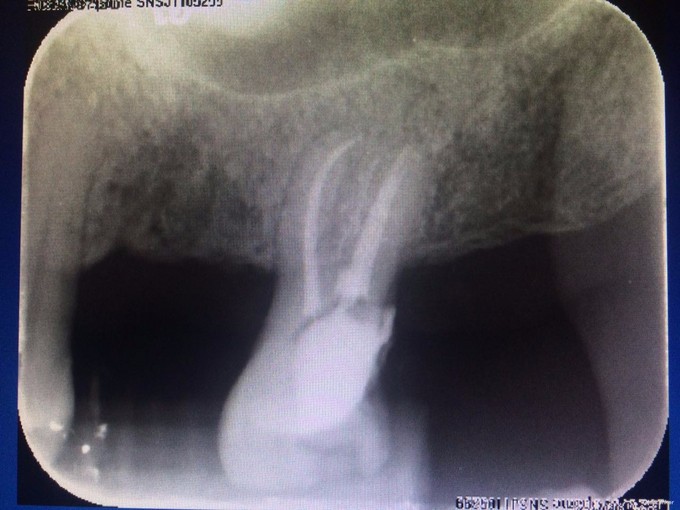

检查:#27 he 面见大量黑色腐质,叩(—),松(I),探(+),冷热测迟缓性疼痛,去除刺激后依旧持续一段时间,电测有活力,牙龈稍红肿,#26,#28已拔除,拔牙创愈合可。 X线示: #27根尖未见明显阴影,牙槽骨吸收至根中1/3

诊断:#27慢性牙髓炎 治疗: #27碧兰麻下开髓、揭全顶,寻找根管口,拔髓,次氯酸钠和双氧水交替超声冲洗,测量工作长度,根管预备,封Ca(OH)糊剂2两周,ZOE暂封。两周后复诊检查,患牙无叩痛,患者无不适,暂封存。去暂封,次氯酸钠和双氧水交替超声冲洗,再次测量工作长度,干燥,热牙胶充填。树脂充填治疗。